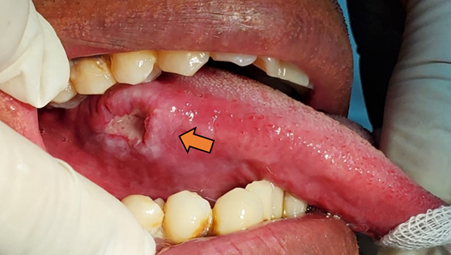

Al examen intraoral, úlcera dolorosa de 10 días de evolución, aspecto crateriforme de 11 x 8 mm, forma irregular, bordes elevados e indurados, rodeada por áreas blanquecinas que no se desprendían al raspado similares a una leucoplasia, fondo de color blanco amarillento por al exudado fibrinopurulento, localizado en el tercio posterior del borde lateral derecho de lengua; a la palpación consistencia renitente y leve tumefacción del sector; el dolor afectaba la movilidad de la lengua provocando limitaciones en la masticación y el habla (Figura 1).

Figura 1. Lesión en borde lateral derecho de lengua. Úlcera de bordes elevados e indurados con fondo blanco amarillento; rodeado por áreas de queratosis (Flecha naranja)